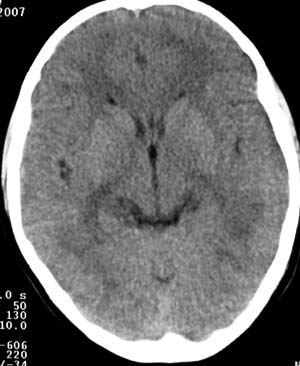

两侧颞枕叶脑白质区多发斑片状低密度灶,考虑脑白质病变;肾上腺脑白质营养不良可能大。

1,发病年龄相符,5-10y。2,临床有视、智力改变。3,病灶发病位置相符;大脑后部白质,侧室三角区周围,对称。

两侧脑室后角旁、丘脑、放射冠、颞顶叶呈对称性片状低密度影,脑室系统、环池、四叠体池、脑桥小脑角池偏大。

病灶从后向前发展,结合临床表现,首先考虑:肾上腺脑白质营养不良。

两侧脑室后角周围髓质,丘脑,放射冠,及颞顶区可见对称的低密度区,侧脑室后角未见明显扩大

诊断:肾上腺营养不良性脑白质病